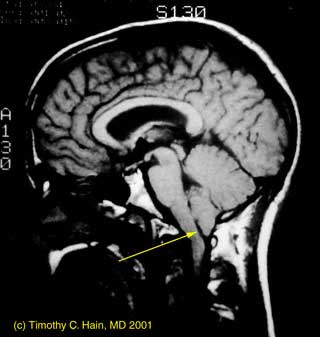

MRI, especially sagittal images, are best for detecting Chiari malformations and syringomyelia

- significance of low-lying tonsils questionable - retraction with age

- cut-off in first 10 years - 6mm below the foramen magnum

- cut-off from 10-30 years - 5mm below foramen magnum

- cut-off after age 30 - 4 mm below foramen magnum

- herniations >12mm are almost invariably symptomatic

- syrinx can also be quite large with little symptoms

- cerebellar tonsils below the foramen magnum, usually 1cm or more

- Chiari I (image at right)